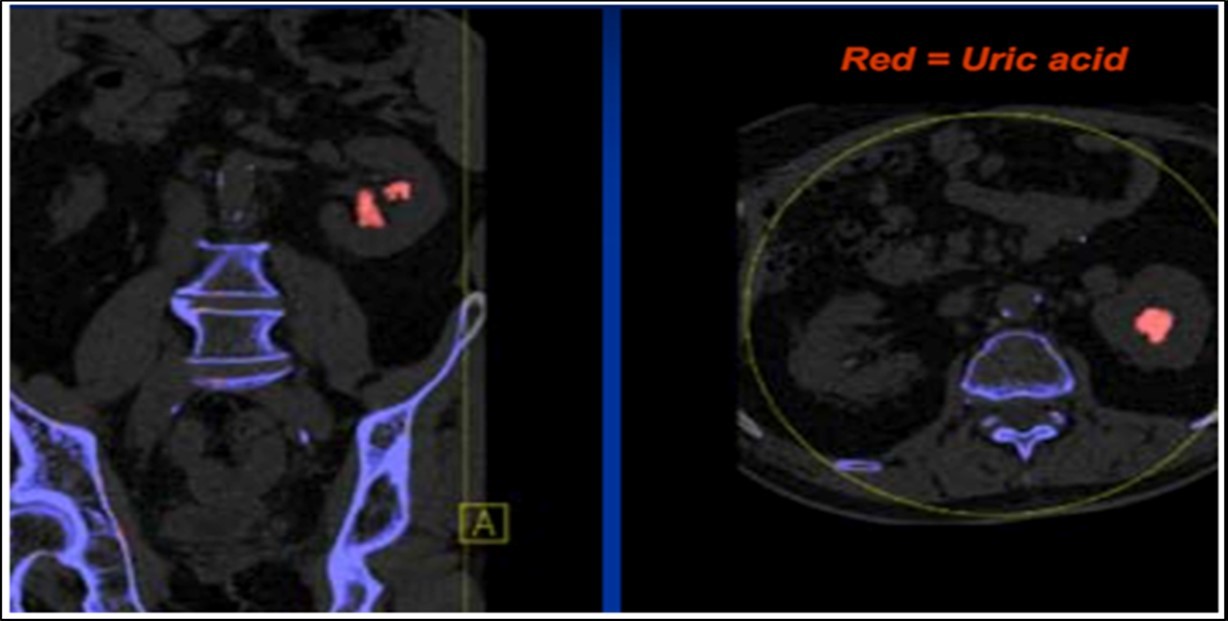

The attenuation difference is shown in colors. In graph 1, the 1.15 ratio represents threshold between uric acid and other stones. If a data point corresponding to a stone with unknown composition falls below this line, the algorithm will characterize such stone as a UA stone and will assign it a predefined red color. And if it falls above the line it will be identified as a non-UA stone and will be shown blue 2.

Stone analysis, together with serum and 24-hour urine metabolic evaluation, can identify the etiology in more than 95% of patients 1. Preoperative prediction of stone type (figure 1 and figure 2) is crucial for therapeutic decision making and follow-up 2, 3, 4, 5, 6. Some studies have reported predictive role of dual energy CT scan for determination of stone type 7, 8, 9.